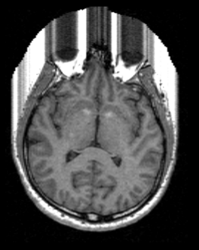

For the following example an image dataset of a human head was used.

After execution of the privacy module there is a additional surface visible on the front of the head surface.

This example shows the data in the 3D view in slicer before and after the usage of two different parameter settings in the module.